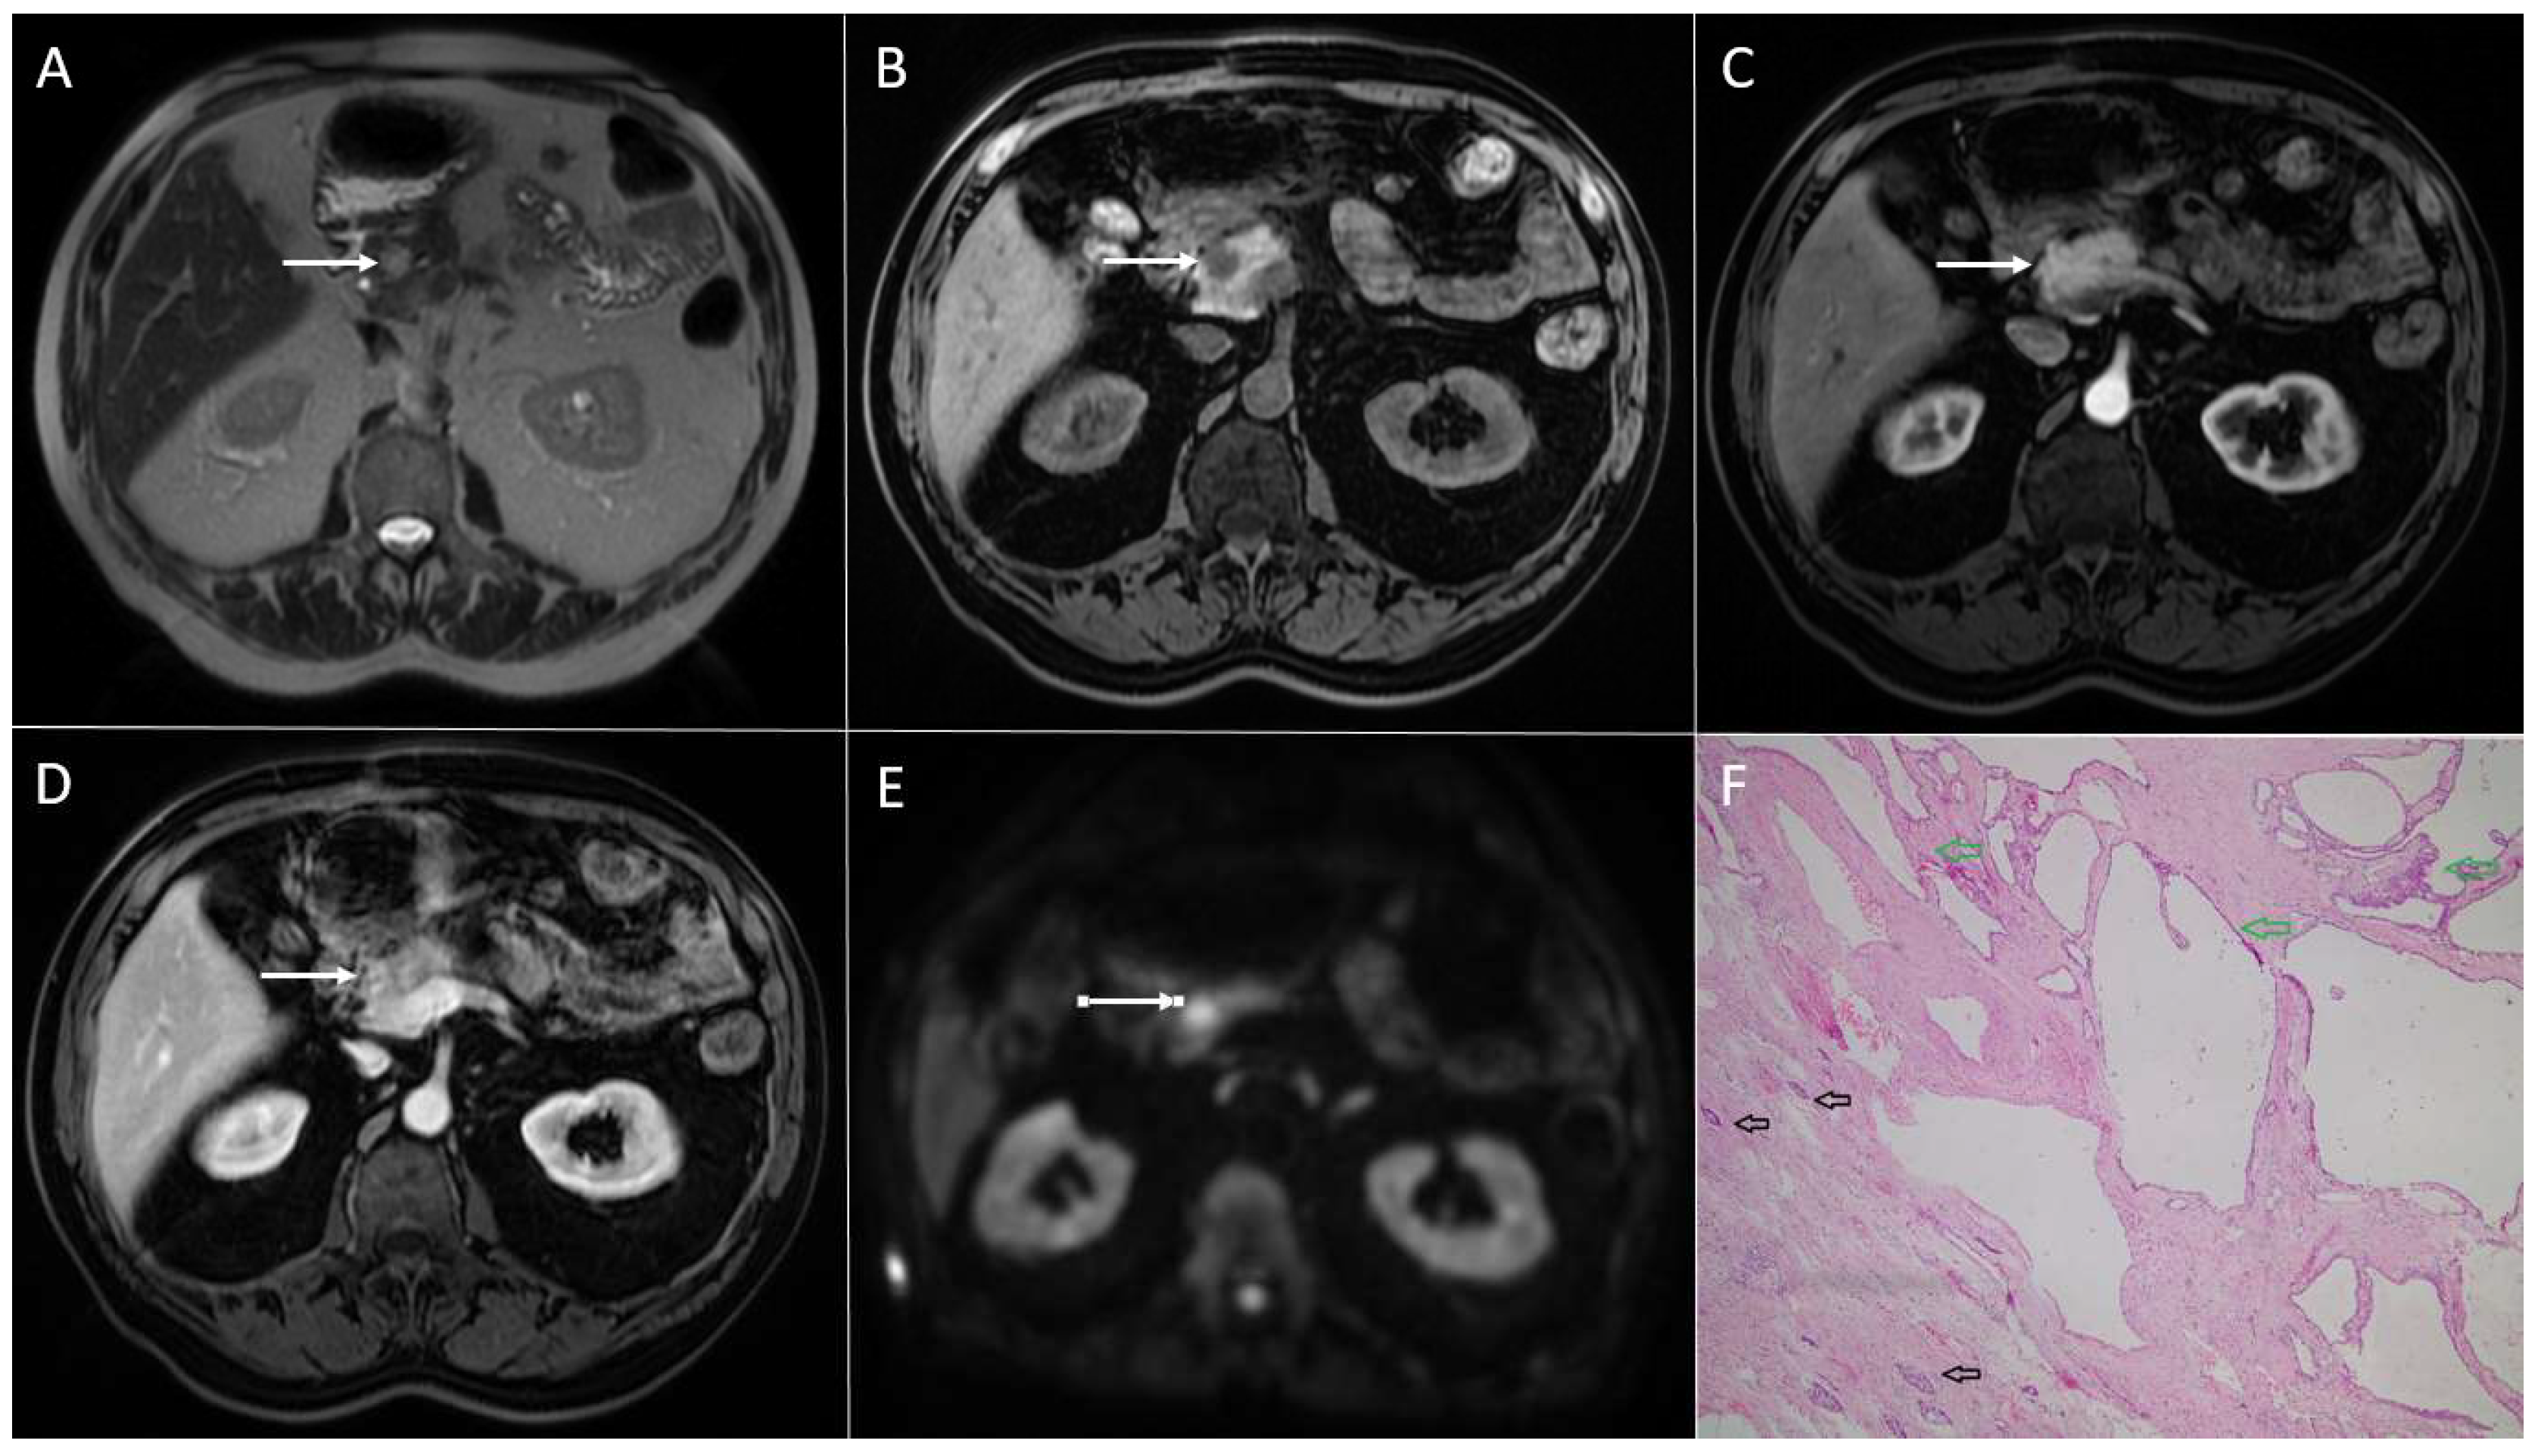

3.3. Intrapancreatic Accessory Spleen